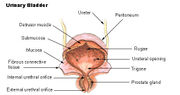

| 3. 5. 2011, 11:59 | Mocovy mechyr.jpg (soubor) |  | 34 kB | Webmaster | (Zdroj: http://en.wikipedia.org/wiki/Urinary_bladder) | 1 |